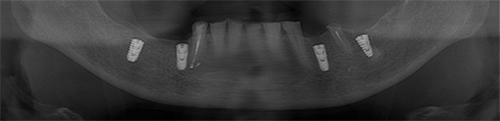

CTデータをもとに三次元的なシミュレーションを行い、補綴主導で埋入ポジションを設計したうえで、専用のサージカルガイドを作製します。

このガイドを実際の手術時に使用することで、術前に立てた埋入位置・角度・深度をより高い精度で再現することが可能となります。

実際の症例でも順次活用を始めており安全で再現性の高いインプラント治療につなげています。